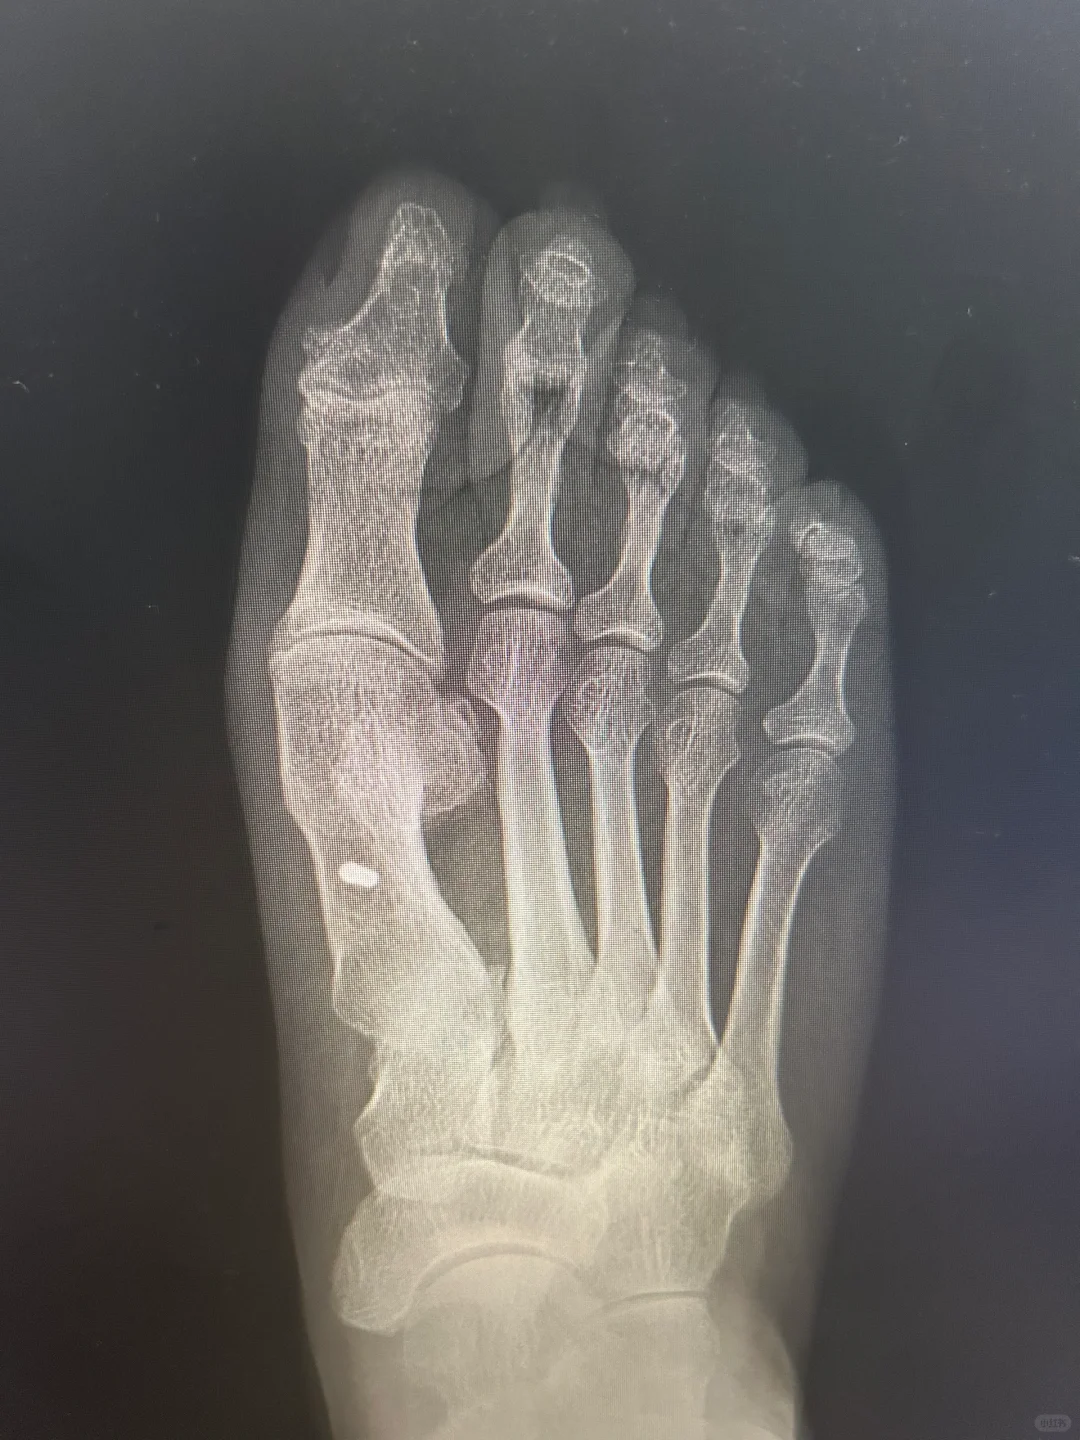

拇外翻术后三年半

手术伤口瘢痕变成白色,术后半年隆起,一年内色深,等2年后慢慢变白。 即使当初缝合愈合并没有那么好,当初没有全部内缝,还有部分外缝的蜈蚣瘢 关节稳定,匹配良好,无不适,没有复发可能 片子上缺损的三角骨区域长满新骨,骨痂下成骨不需要担心。 新骨密度高,都是气质骨,所以强度远高于术前